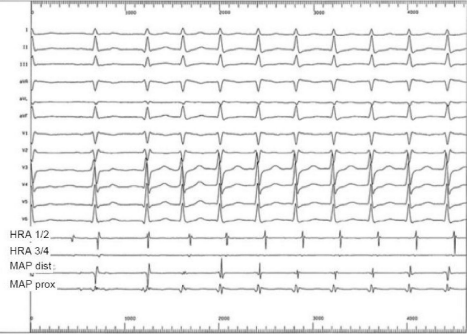

O exame abaixo sugere como diagnóstico:

Legenda: HRA = eletrodos 1 e 2, 3 e 4 atriais altos; MAP = cateter de ablação no ventrículo.